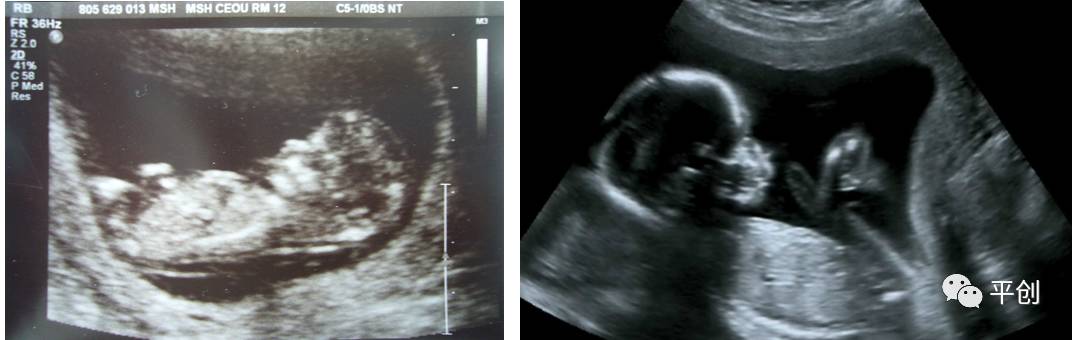

更準確的醫(yī)學診斷,來自B超檢查結(jié)果的輔助,準確的B超檢查結(jié)果,來自B超醫(yī)生看到的B超圖像,清晰的B超成像,來自好的耦合劑。所以說,好的耦合劑對B超的成像很重要。

而影響B(tài)超檢查成像的因素有兩點,一是來自好的探頭,二是來自優(yōu)質(zhì)的耦合劑。如果這兩個產(chǎn)品其中有一個質(zhì)量不過關,即對B超成像有一定程度的影響,可能會有成像不清楚,醫(yī)生無法準確判斷所檢查器官的實際病變,嚴重的有可能度至醫(yī)生誤診的后果。

所生產(chǎn)出來的耦合劑無雜質(zhì)、透明度高、不易干,不化水,易偶合、易擦凈,透聲性超過國家標準的50%(數(shù)據(jù)通過國家指定的第三方檢測機構檢測結(jié)果所得),完全地解決了成像不清晰的難題。

安創(chuàng)安必潔耦合劑已經(jīng)在廣東省人民醫(yī)院、南方醫(yī)院、中山大學附屬第一醫(yī)院等全國各三甲醫(yī)院使用,并得到了各醫(yī)院的一致認可,解決了其它品牌耦合劑的偶合性差、透聲功能低,成像不清晰的問題,減少了B超結(jié)果誤診的機率,同時也解決了短期內(nèi)要多次尋找耦合劑品牌的煩惱,所以得到了各合作醫(yī)院的聯(lián)合推薦使用:“好的耦合劑,選用安創(chuàng)安必潔消毒耦合劑。